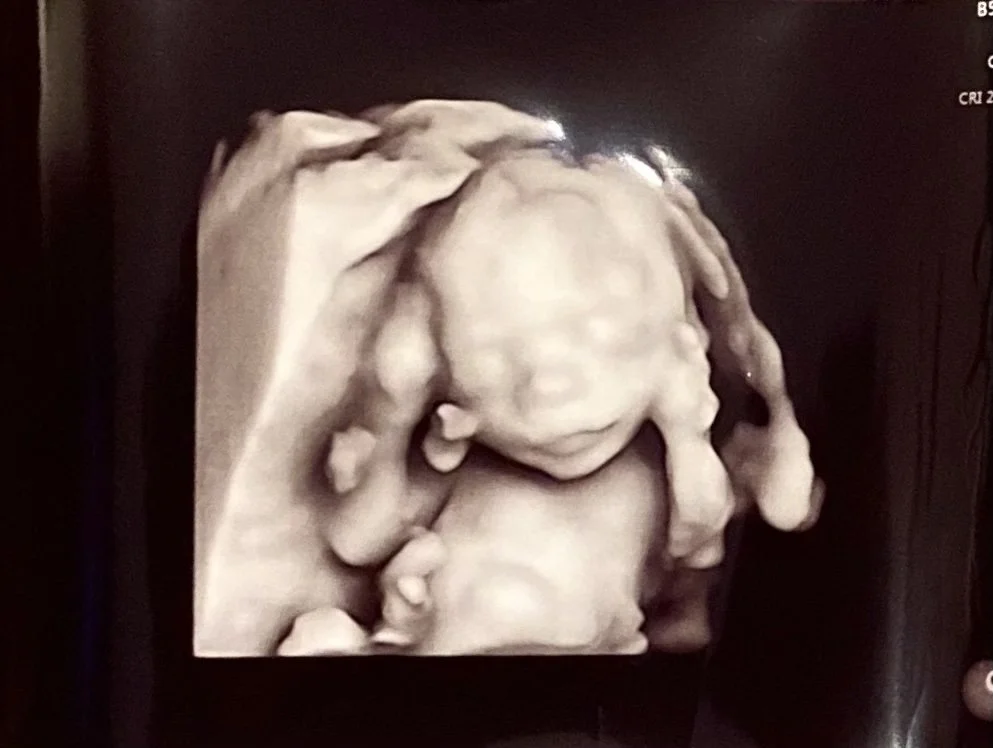

Imagine you are Alice in Wonderland for a moment. Remember the part where she shrinks very tiny, then grows very large? At one brief moment, when she gets too tall to fit in the house, her head tilts to the left and she curls her body to the side to fill any extra space in the house before she shrinks again.

This is similar to what can happen with a baby inside the womb, but a major difference is that the baby doesn’t shrink back down! Babies only continue to grow and develop. While not always what happens, this positioning of head tilted to one side, maybe looking one direction, and body curved into a C-shape is what can lead to muscle tightness throughout the body over time as the baby continues to grow to full-term.

As babies continue to grow, they can be restricted by available room which causes some muscles to develop to longer/full length and others to develop in a shorter/restricted length. While there is nothing to prevent this type of restriction from occurring, early intervention (even days after birth) can be drastically helpful in correcting muscle length differences and promoting symmetrical and equal movement throughout the body. Tight muscles typically do not stretch out on their own, and can make motor skills such as tummy time, rolling, sitting, crawling, and walking more difficult.